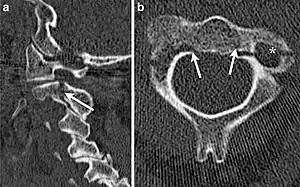

Hangman's fracture

Hangman's fracture is the colloquial name given to a fracture of both pedicles, or pars interarticulares, of the axis vertebra (C2).

| CT scan of hangman's fracture | |